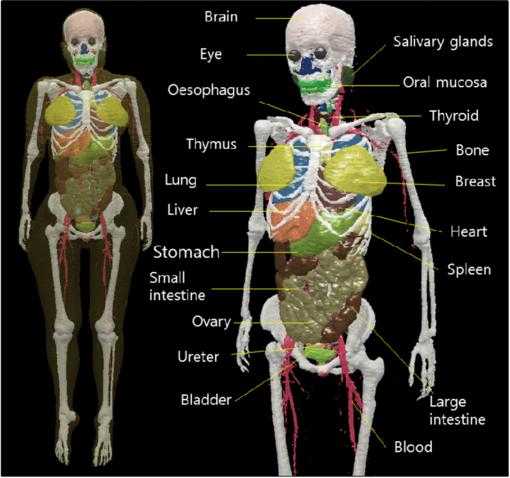

In the present study, a Korean adult female voxel phantom (HDRK-Woman; figure 5) was constructed using serially sectioned high-resolution color photographic images of a Korean female cadaver. The phantom is 161 cm in height and 54 kg in weight, which matches the figures in the reference Korean data. The voxel resolution is 2.0351 mm × 2.0351 mm × 2.0747 mm. The phantom is composed of 261 × 109 × 825 voxels ( = 23,470,425 voxels). The voxel phantom has 40 organs and tissues, including 27 organs for effective-dose calculations.

Figure 5. HDRK-Woman constructed in present study.

Download figure:

Standard image High-resolution imageTable 1 lists the phantom's organs and tissues alongside the reference Korean data. It is evident that the masses are closely matched to the reference Korean data, except for several organs, such as skin, blood, eye lens, tongue, trachea, and bronchi, due to the finite voxel resolution. The skin mass was 74.3% larger than that of the reference Korean data, even though the skin was defined as just a single voxel layer enveloping the phantom. The HDRK-Man and other phantoms, including the ICRP reference phantoms, exhibit the same problems. ICRP Publication 110 (ICRP 2009) indicates that several thin or small organs were not adjusted to match the reference values due to the finite voxel resolution.